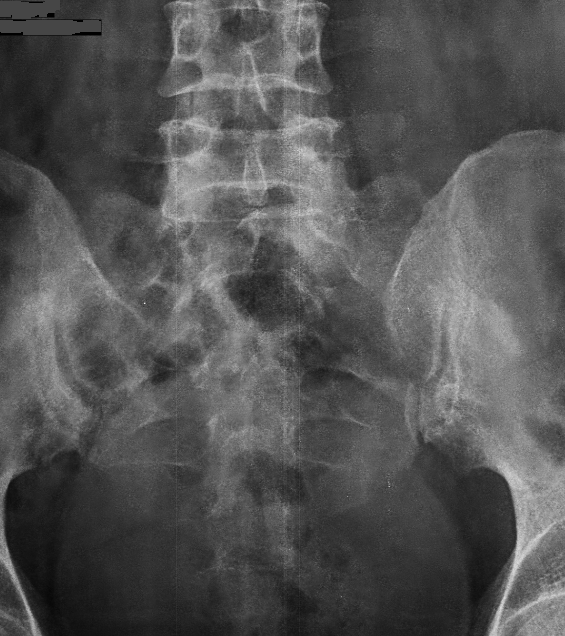

Sacral fracture | Radiology Case | Radiopaedia.org

Sacral fracture | Radiology Case | Radiopaedia.org from images.radiopaedia.org

Fatigue sacral stress fractures appeared more commonly in women than in men ( p<0.001). Stress fractures of sacrum are rare overuse injuries. Tenderness along the sacrum or si joint.

A sacral stress fracture is a small break in the sacrum.

Factors that can contribute to this type of fracture include Mri is highly sensitive and specific for the diagnosis of sacral stress fractures. Bone scan, mri or ct can be used to detect a sacral stress fracture; Slipman cw, gilchrist rv, isaac z, lenrow da, chou lh. Role of mri in the diagnosis of insufficiency fractures of the sacrum and acetabular roof. Ct and mri findings suggest that sacral stress fractures occur due to repeated compressive forces resulting in shear microfractures of the trabecular bone10. First described by lourie in 1982 1. Mri is the most sensitive modality for detecting stress fracture, and may also be useful for differentiating ligamentous/cartilaginous injury from a bony injury. Sacral insufficiency fractures (sif) is a common cause of debilitating back pain in the elderly. The sacrum is a large triangular bone at base of the spine. Sacral coronal magnetic resonance imaging (mri) of the left sacral ala revealed an oblique lineal signal void surrounding bone marrow edema. The combination of low bone density and increased activity blurs the boundary between fatigue and insufficiency fractures in many runners. Early mri is recommended if a medial malleolar stress fracture is suspected. Bone scans can show evidence of stress fracture within a few days upon the onset of symptoms. They are difficult to diagnose, because purpose: Sacral insufficiency fractures (sifs) result from normal stress applied to abnormal bone; Typical mri appearance of stress fracture includes: